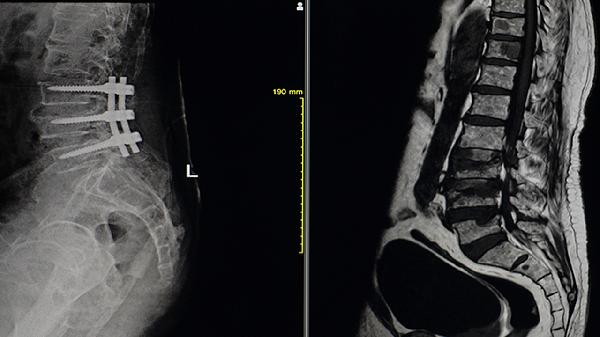

全髋关节置换术适用于严重髋关节强直患者,可恢复活动功能。脊柱矫形术针对驼背畸形,需评估心肺功能后实施。微创椎间孔镜手术能解除神经压迫,术后需配合康复训练。手术风险包括感染、假体松动等,需严格掌握适应证。